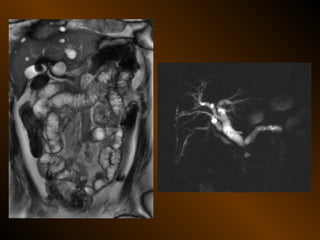

Cộng hưởng từ

• Căng giãn ruột non

• Căng giãn đại tràng

CĂNG GIÃN ỐNG TIÊU HÓA